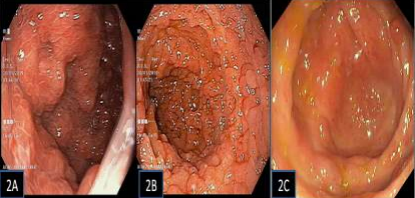

A 42-year-old woman has had abdominal pain, vomiting, and loose stools (10 to 12 times per day) for the past 6 months. She has also noticed hair loss, bad breath, changes in her nails, and dark skin all over her body. She has also had bloating, extreme fatigue, and loss of appetite for a month. She reports no bloody stools, fever, arthritis, weakness, or mouth sores. She has no family history of similar illnesses. On examination, he was unconscious but agitated. He has a low body weight (19.6 Kg/m2), pale, dark skin all over the body, frontal alopecia, diffuse skin pigmentation and dystrophic finger and toenails (Figure 1). Blood test showed red blood, hemoglobin 9.5g/dL (12 - 14 gm/dL; - 4.5 gm/dL), persistent hypokalemia, serum concentration 2.8-3.2 meq/dL). Small amount of pleural effusion and mild ascites. Disease markers including ESR and CRP are within normal limits. HIV serology and ANA were negative. Stool tests and immunoglobulin profile were within normal limits. Esophagogastroduodenoscopy (EGD) revealed multiple small masses throughout the stomach (Figure 2A) and duodenum (Figure 2B). Mucosal sections were obtained from the stomach and duodenal polyps. Ileocolonoscopy also revealed multiple intestinal polyps of varying sizes (Figure 2C) and a large polyp (approximately 1.5 cm) in the terminal ileum. Segmental biopsies were performed from polyps and normal mucosa. Colonic polyp section results revealed hamartomatous polyps and tubular adenomas with mild dysplasia (Figure 3A). Mucosal findings were remarkable, with marked edema, mild lymphoplasmacytic infiltration, and cystically dilated tumor with concentrated mucin. (Figure 3B) Gastric and duodenal biopsies also showed hamartomatous polyps, and immunohistochemistry showed a few plasma cells positive for IgG4. It is classified as gastrointestinal polyposis. The combination of the polyposis, ectodermal features, and histopathologic findings led to a definitive diagnosis of Clonket-Canada syndrome. We gave her oral prednisolone 40 mg/day for 1 month, then tapered by 5 mg every 2 weeks to reach a final treatment dose of 5 mg/day for 1 month. She has a severe reaction to steroids. Azathioprine was used with a steroid dose of 50 mg/day for 3 months and continued thereafter. After 3 months of treatment, stool frequency and consistency improved. Generalized edema decreased, appetite increased, and hyperpigmentation decreased. The patient is currently taking azathioprine 50 mg. There has been no recurrence in the last 36 months.

Figure 2: Endoscopic images: Gastric body numerous polyps (2A), Duodenal / D2 polyps (2B), Colonic polyps (2C).